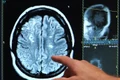

0Un șofer de ambulanță, de 57 de ani, de la substația de ambulanță din Rădăuți, SAJ Suceava, a suferit un accident vascular cerebral (AVC) în timp ce se afla la volan, în timpul unei misiuni de salvare de sâmbătă, potrivit Monitorul de Suceava.

Conform declarațiilor purtătorului de cuvânt al SAJ Suceava, dr. Adriana Morari, ambulanțierul a suferit un accident vascular cerebral cu deficit neurologic, însă nu și-a pierdut conștiența.

„S-a intervenit rapid, ajungând la Suceava, unde este centrul regional de stroke”, a declarat dr. Morari.